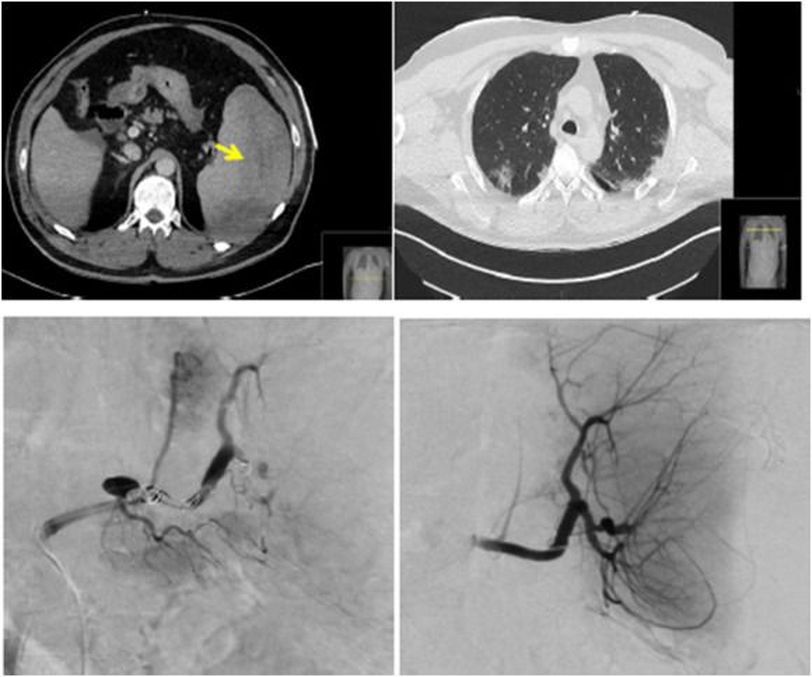

Just like CoVid-19, which is an expeditiously evolving situation, the presentation of said infection is also changing rapidly. Initially, SARS-CoV2 was thought to damage only respiratory system, however, the systemic involvement and enteric symptoms are also associated with CoVid-19. According to the literature, CoVid-19 directly affects spleen and lymph nodes, resulting in subsequent splenic nodule atrophy and lymphocyte depletion. These conditions result in microvascular thrombosis and necrosis of spleen. A journal reported a case where a previously healthy 57 years old male CoVid-19 positive patient presented to ER with altered state of consciousness with raised respiratory rate and shortness of breath at rest. Patient also gave history of abdominal pain. On examination, crackles were auscultated on both lungs. The abdomen was tender. Patient was hypotensive and tachycardic with 128 bpm. CT was suggestive of hemoperitoneum. Extracapsular rupture of spleen was noticed. All possible causes of splenic rupture, including trauma, were ruled out. Hemodynamic and ventilatory support was provided. Splenic artery embolization was performed to control bleeding. The patient recovered after 24 days. Ruling out all the possible causes indicated possibility of covid-19 as prime culprit in splenic rupture in patient suffering from covid-19 infection. Source Atraumatic splenic rupture due to covid-19 infection https://www.sciencedirect.com/science/article/pii/S2590170220300297 Image taken from https://www.sciencedirect.com/science/article/pii/S2590170220300297